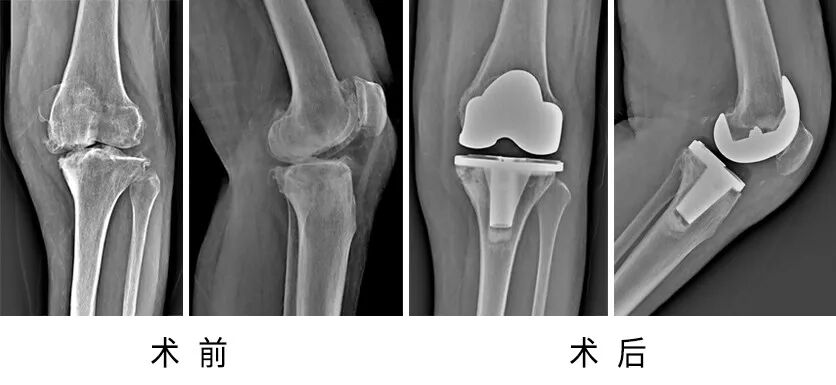

78歲的余奶奶,2年前出現(xiàn)左膝關(guān)節(jié)腫脹、疼痛,活動(dòng)輕度受限,休息后癥狀能夠緩解,近3個(gè)月,余奶奶自覺左膝關(guān)節(jié)腫痛癥狀較前明顯加重,不能行走,休息后癥狀不能緩解。

經(jīng)人介紹,余奶奶找到了省級(jí)知名骨科專家、邦爾骨科集團(tuán)首席專家、嘉興邦爾骨科醫(yī)院院長(zhǎng)趙凱教授,診斷為“左膝骨性關(guān)節(jié)炎”。

趙凱教授帶領(lǐng)四肢關(guān)節(jié)組團(tuán)隊(duì),為余奶奶順利完成了“左側(cè)人工膝關(guān)節(jié)表面置換術(shù)”,術(shù)后余奶奶行走自如。

術(shù)前術(shù)后對(duì)比圖